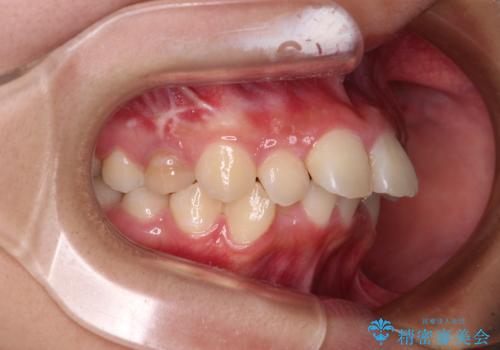

- 下唇の上に乗っかってしまうくらい前歯が飛び出していることを気にして来院された患者様です。

唇を閉じようとするとオトガイ部に力が入ってしまい、うまく閉じることができない状態であったため、上下左右の第一小臼歯4本を抜歯して、ワイヤー装置にて矯正治療を行うこととしました。

飛び出した前歯はしっかりと引っ込み、横顔の印象が大きく変化しました。